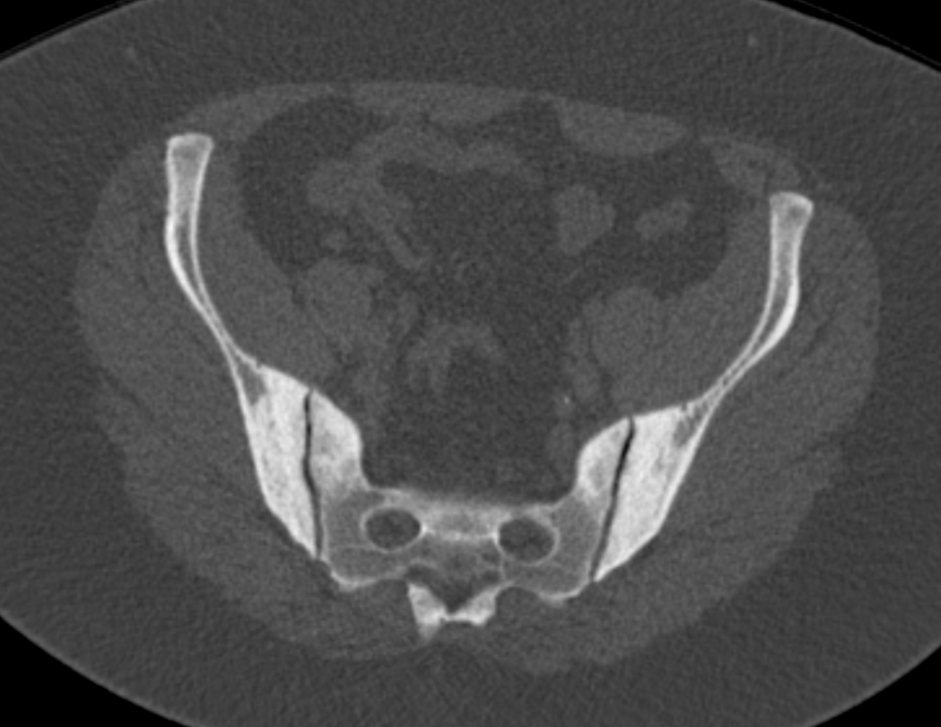

3. Osteitis condensans ilii